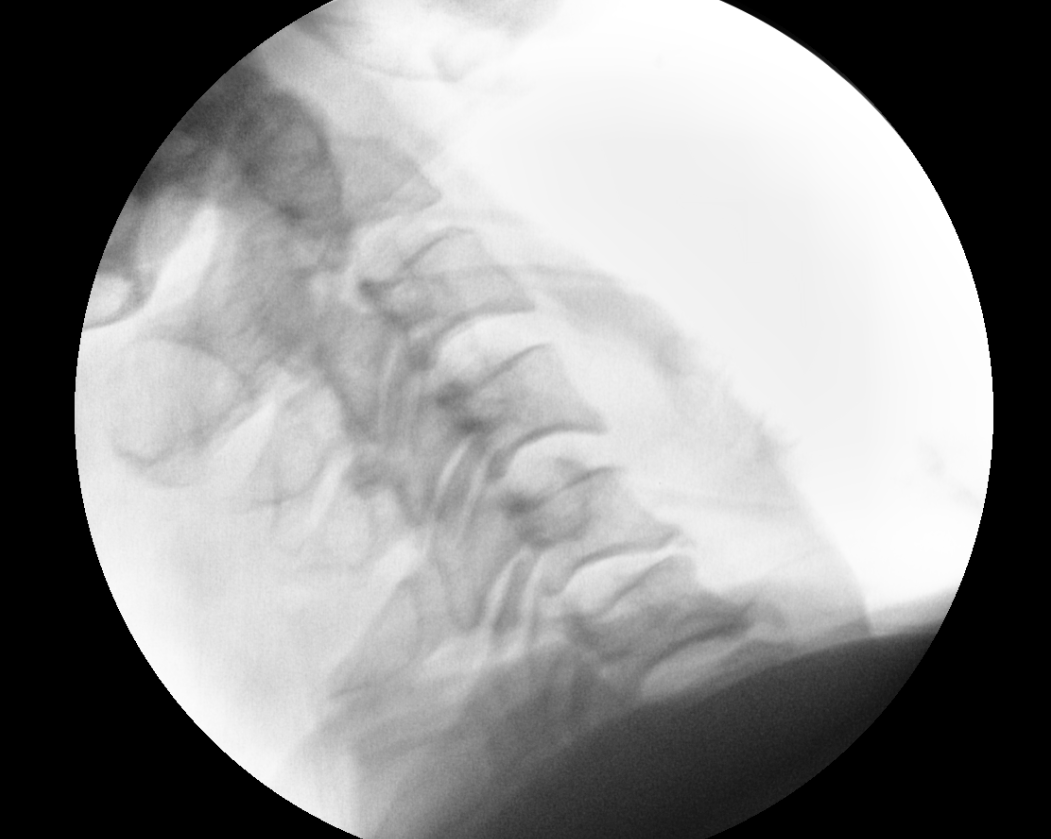

x ray 측면에서 보면 경추 5/6 후관절 탈골이 확인이 됨.

그 다음날에 점심정도에 다시 병원에 오셔서 수술 정하셨다고 하여, 수술방에 올라가 reduction 시행함

reduction 된 것을 확인 하였음.